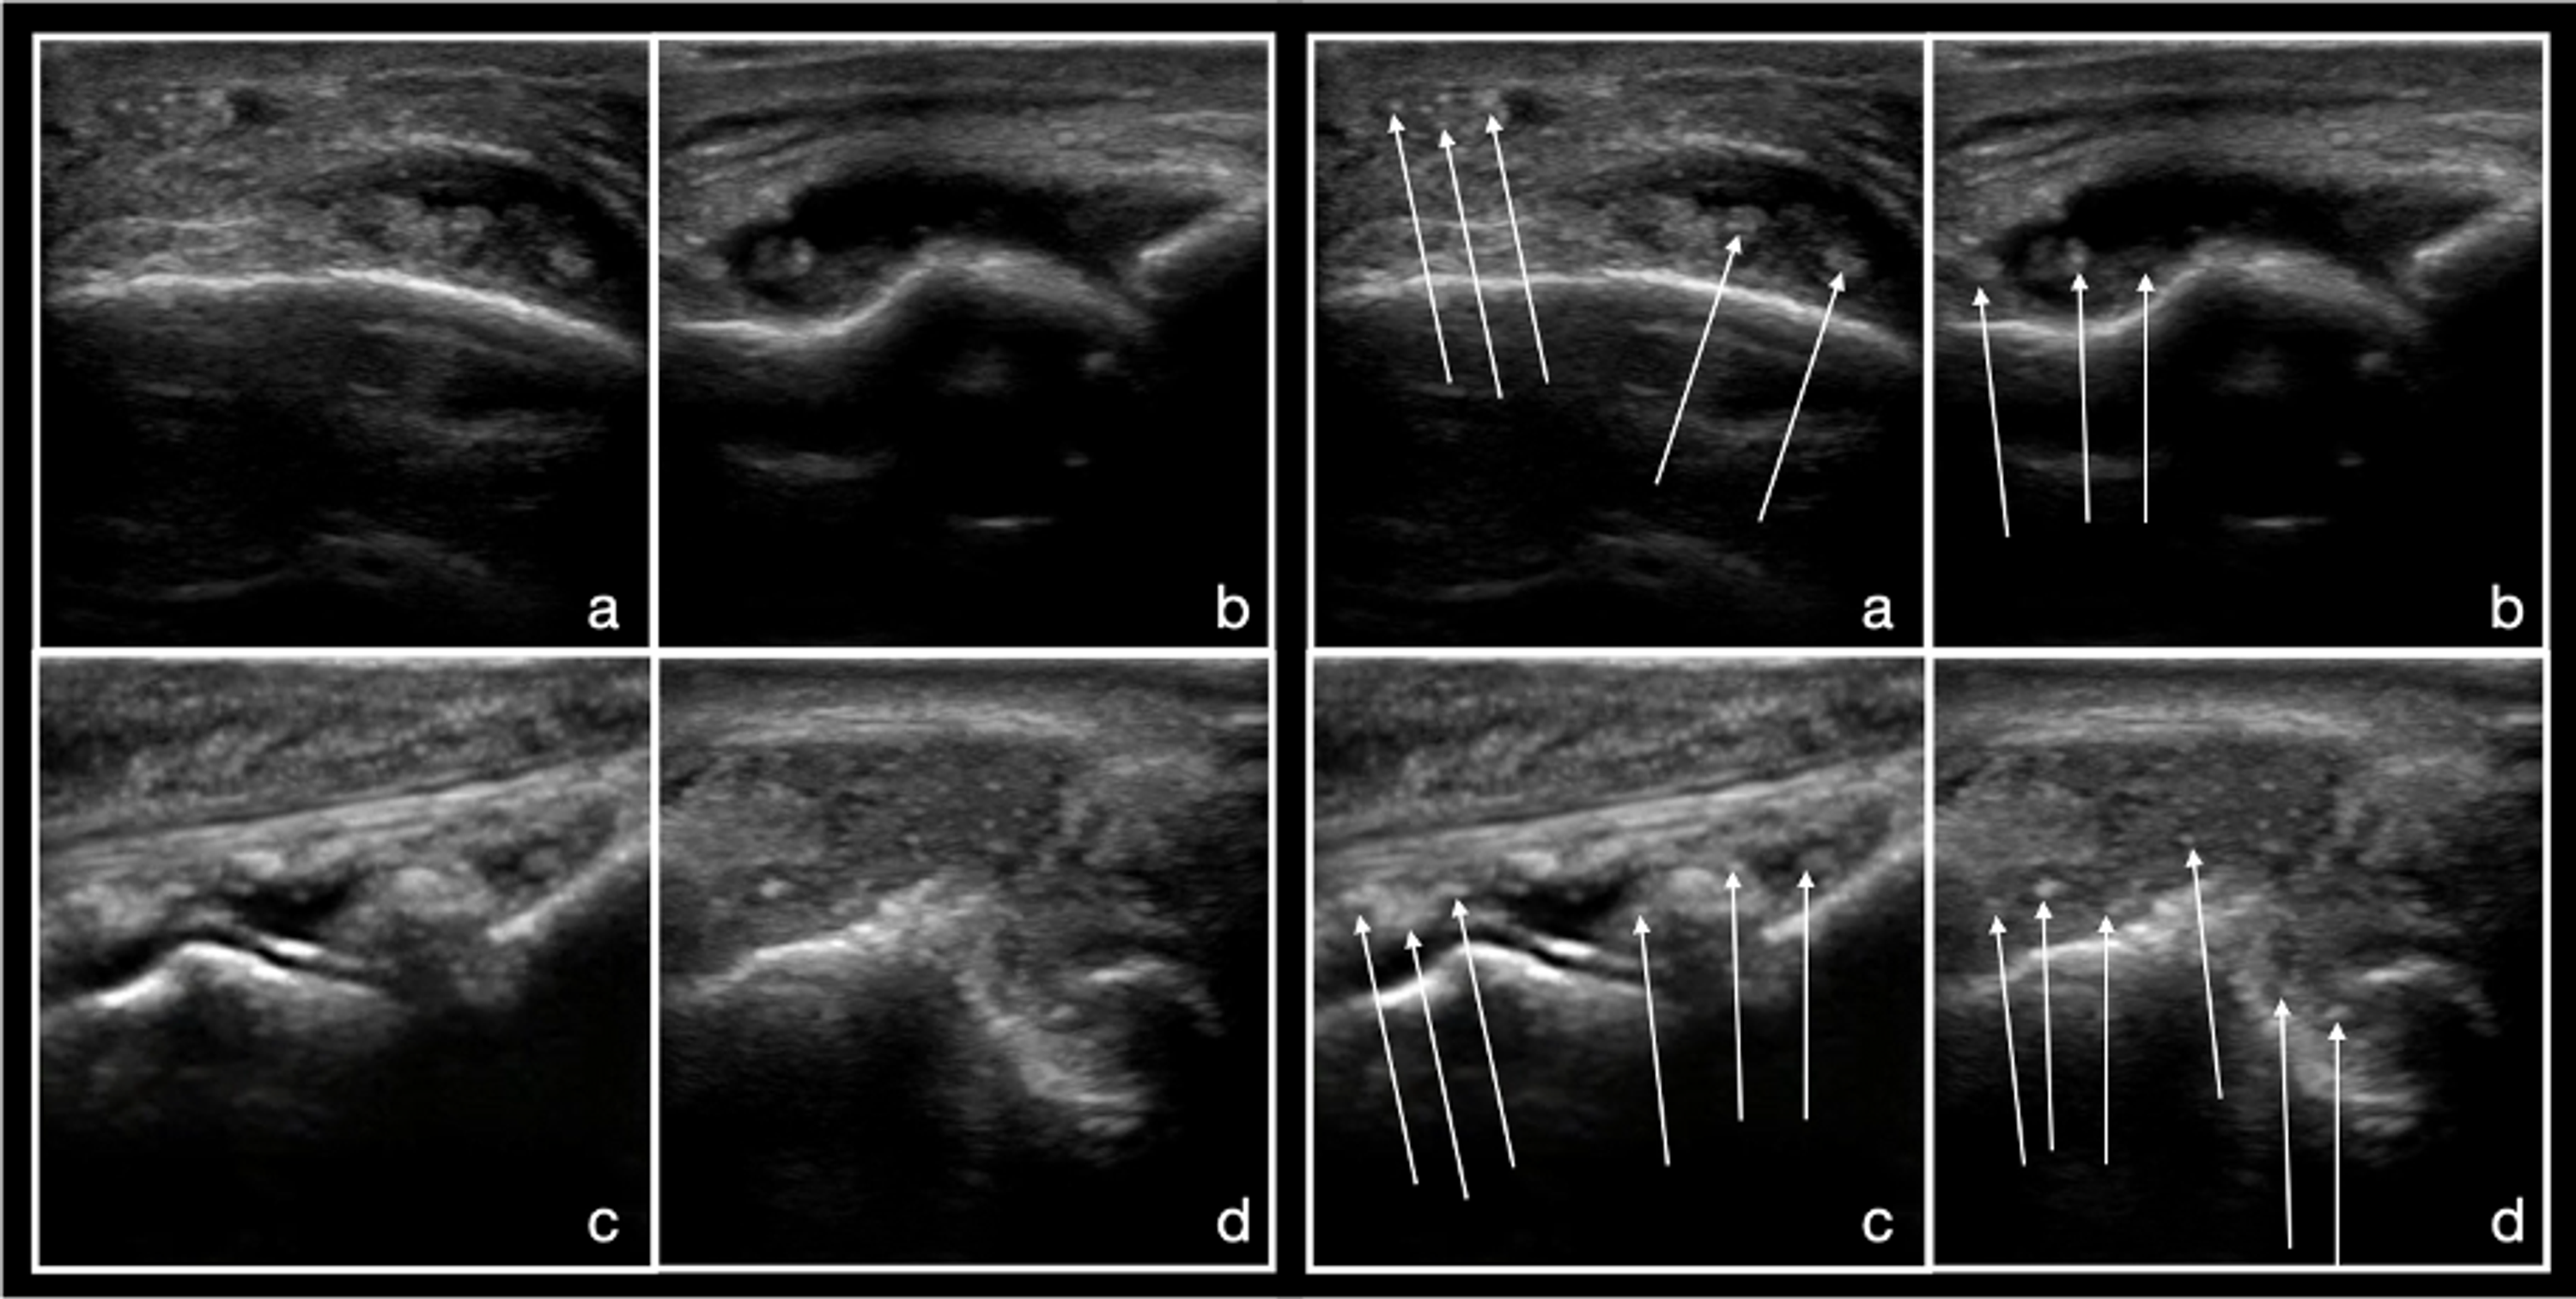

___Gouty Arthritis Calcification along the superior layer of hyaline Gout Arthritis Ultrasound ultrasound scans have a diagnostic role in assessing gouty joints. to explore the role of musculoskeletal ultrasound (msus) in the differential diagnosis of gouty arthritis. The american college of physicians (acp) developed this guideline to present the evidence and. because of the inherent difficulty in obtaining an adequate sample, ultrasound has been investigated as a diagnostic tool.. Gout Arthritis Ultrasound.

Sonographic Findings in Gouty Arthritis Diagnostic Value and Gout Arthritis Ultrasound to explore the role of musculoskeletal ultrasound (msus) in the differential diagnosis of gouty arthritis. The american college of physicians (acp) developed this guideline to present the evidence and. because of the inherent difficulty in obtaining an adequate sample, ultrasound has been investigated as a diagnostic tool. ultrasound scans have a diagnostic role in assessing gouty joints.. Gout Arthritis Ultrasound.